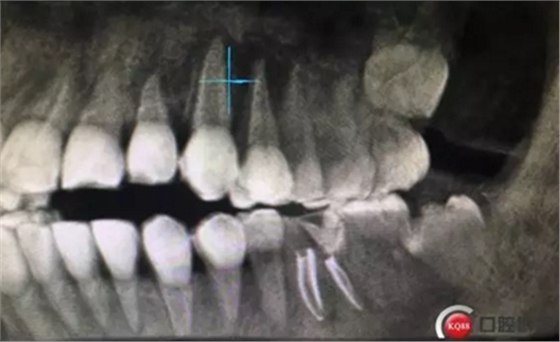

這是折線的位置,右是拔出的牙齒碎片。很明顯折裂波及遠(yuǎn)中頰根。

先去了充填物,去腐,牙齦電切。根折根上段少量,沒有破壞根管結(jié)構(gòu)。選擇保留患牙。

根管治療完成攝片